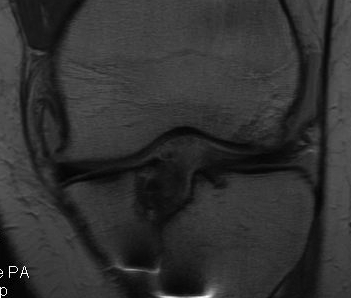

Graft rupture best seen on T1

B. Biological Failure

Failed ligamentisation

Infection